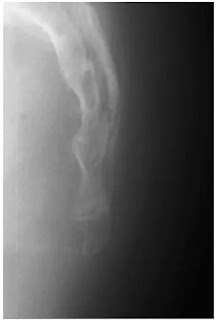

Coccyx lateral projection

Patient को bucky table पर किसी भी एक तरफ लेटाया जाता हैं। coccyx को palpate करके bucky की midline में रखते है। भुजाओं को उठाकर हाथों को pillow पर रखते है। knee तथा hips को stability के लिए हल्का सा flexed करते है। trunk का dorsal aspect कैसेट से right angle पर होना चाहिए। इसका आकलन iliac crest या posterior superior iliac spines को palpate करके किया जाता हैं। map Bucky के समांतर होना चाहिए। cassette के centred को coccyx के level पर central ray के अनुरूप रखते है।

Central ray को sacrum के long axis के right angle पर स्पर्शनीय coccyx की तरफ निर्देशित करते है।